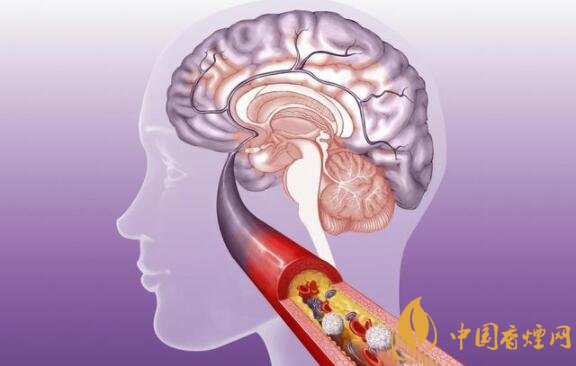

有毒物质就有100多种,点燃后产生的一氧化氮、一氧化碳、二氧化碳、烟碱、焦油、氨等,其中一氧化碳可以让动脉内反应过强性内皮细胞中的肌球蛋白收缩,增强血管壁通透性,引发脂蛋白沉积在血管壁,并聚集在血小板,进而诱发动脉硬化。

除此之外,吸烟后吸入的尼古丁还会促使肾上腺素与去甲肾上腺素释放,引发血管痉挛或收缩,出现血流阻力增大,导致血管壁受损,更容易出现动脉粥样硬化血管狭窄。当肾上腺素促使反应国强内皮细胞的肌球蛋白收缩后,容易导致动脉硬化,进而易形成脑血栓,发生中风。